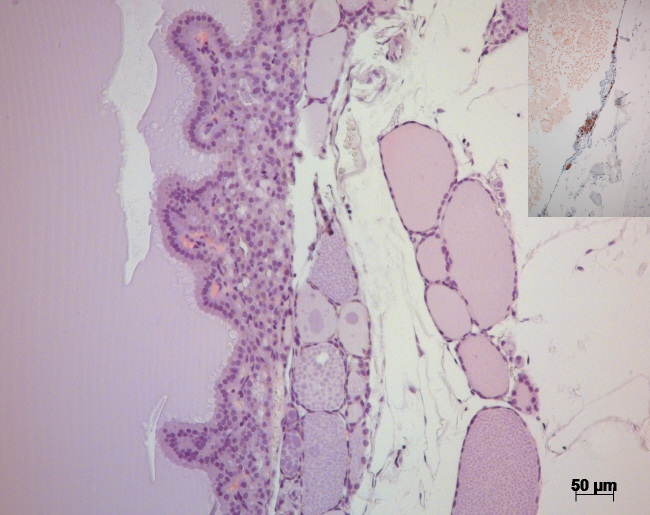

Two cystadenomas and one solid adenoma of the thyroid gland in a 27-year-old female African green monkey (Chlorocebus aethiops) are described here. Histologically, the solid adenoma was classified as a well-defined solid follicular adenoma of microfollicular type. The solid adenoma was positive for thyroglobulin in immunohistochemistry staining, whereas the cystadenomas stained positive for both thyroglobulin and calcitonin. No evidence of excess hormone production related to the tumor presence was detected.